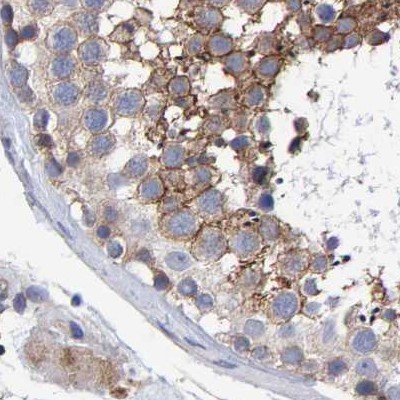

Immunohistochemistry analysis in human cerebral cortex and pancreas tissues using Anti-EFR3A antibody. Corresponding EFR3A RNA-seq data are presented for the same tissues.